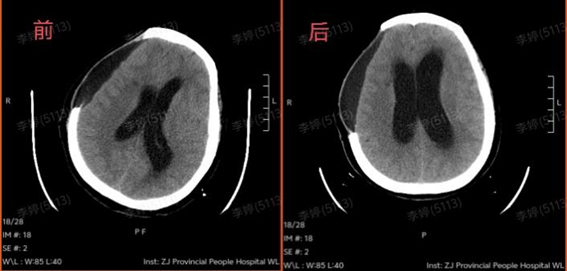

全家人也在积极配合。努力1个月后,王阿姨睁眼了,但眼神呆呆的,叫也没反应,手脚也不怎么动,好像整个人被“定”住了。头颅CT复查发现脑积水加重,脑脊液排不出,压住大脑,影响康复效果。

第一步:先“通水管”。神经外科为王阿姨做了颅骨修补和脑积水引流手术,把“堵住”的问题解决了。